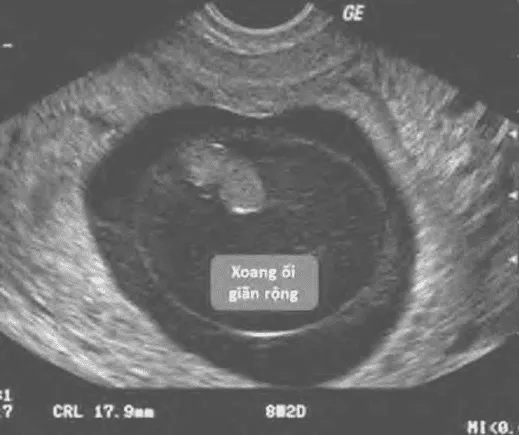

- Xoang ối giãn rộng (expanded amnion sign).

Triệu chứng ra máu, đau bụng, cổ tử cung đóng. Dấu hiệu siêu âm dự báo (không khẳng định) bao gồm:

- Không thấy phôi sau 6 tuần vô kinh.

- Yolk-sac giãn > 7 mm.

- (MSD - CRL) < 5 mm.